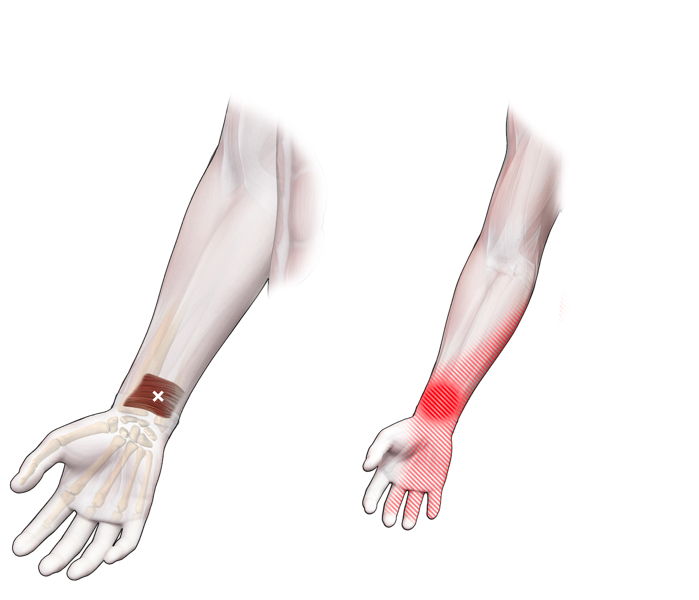

Klachtgebied

Klachten

klachten

Spieren (Nederlands)

Spieren (nederlands)

Spieren (Latijn)

Spieren (latijn)

Trefwoorden

Trefwoorden